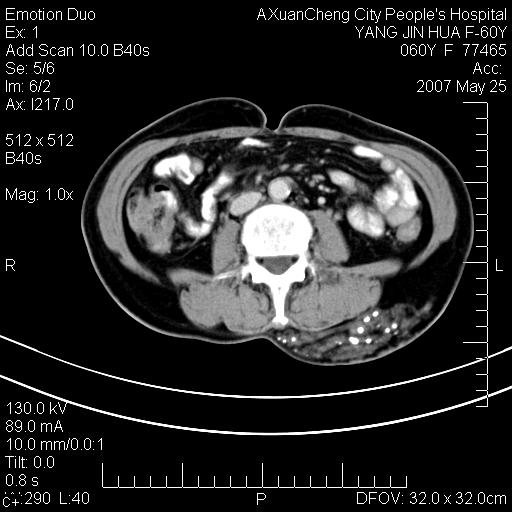

发现左侧腰背部包块40余年,逐渐长大,质软,局部表面可见扩张的血管影

左背部皮下良性肿瘤,密度不均,边界不清,内有脂肪、钙化,增强扫描无明显强化,血管平滑肌脂肪瘤?进一步诊断有困难,建议穿刺活检。

左侧背部皮下混杂密度肿块,结构较疏松,边缘欠光整,内有多发斑点状钙化,考虑:皮下血管瘤。

1.考虑左腰部皮下平滑肌脂肪瘤可能性大;

2.位置特殊,不除外畸胎瘤及错构瘤可能;

3.另骨化性肌炎应在考虑范围之内,请追问病史;

还是考虑皮下血管瘤,强化不明显可能跟大量血栓形成有关,好多战友考虑血管平滑肌脂肪瘤,血管平滑肌脂肪瘤的血管就不强化么?只要有血管就都应该强化。